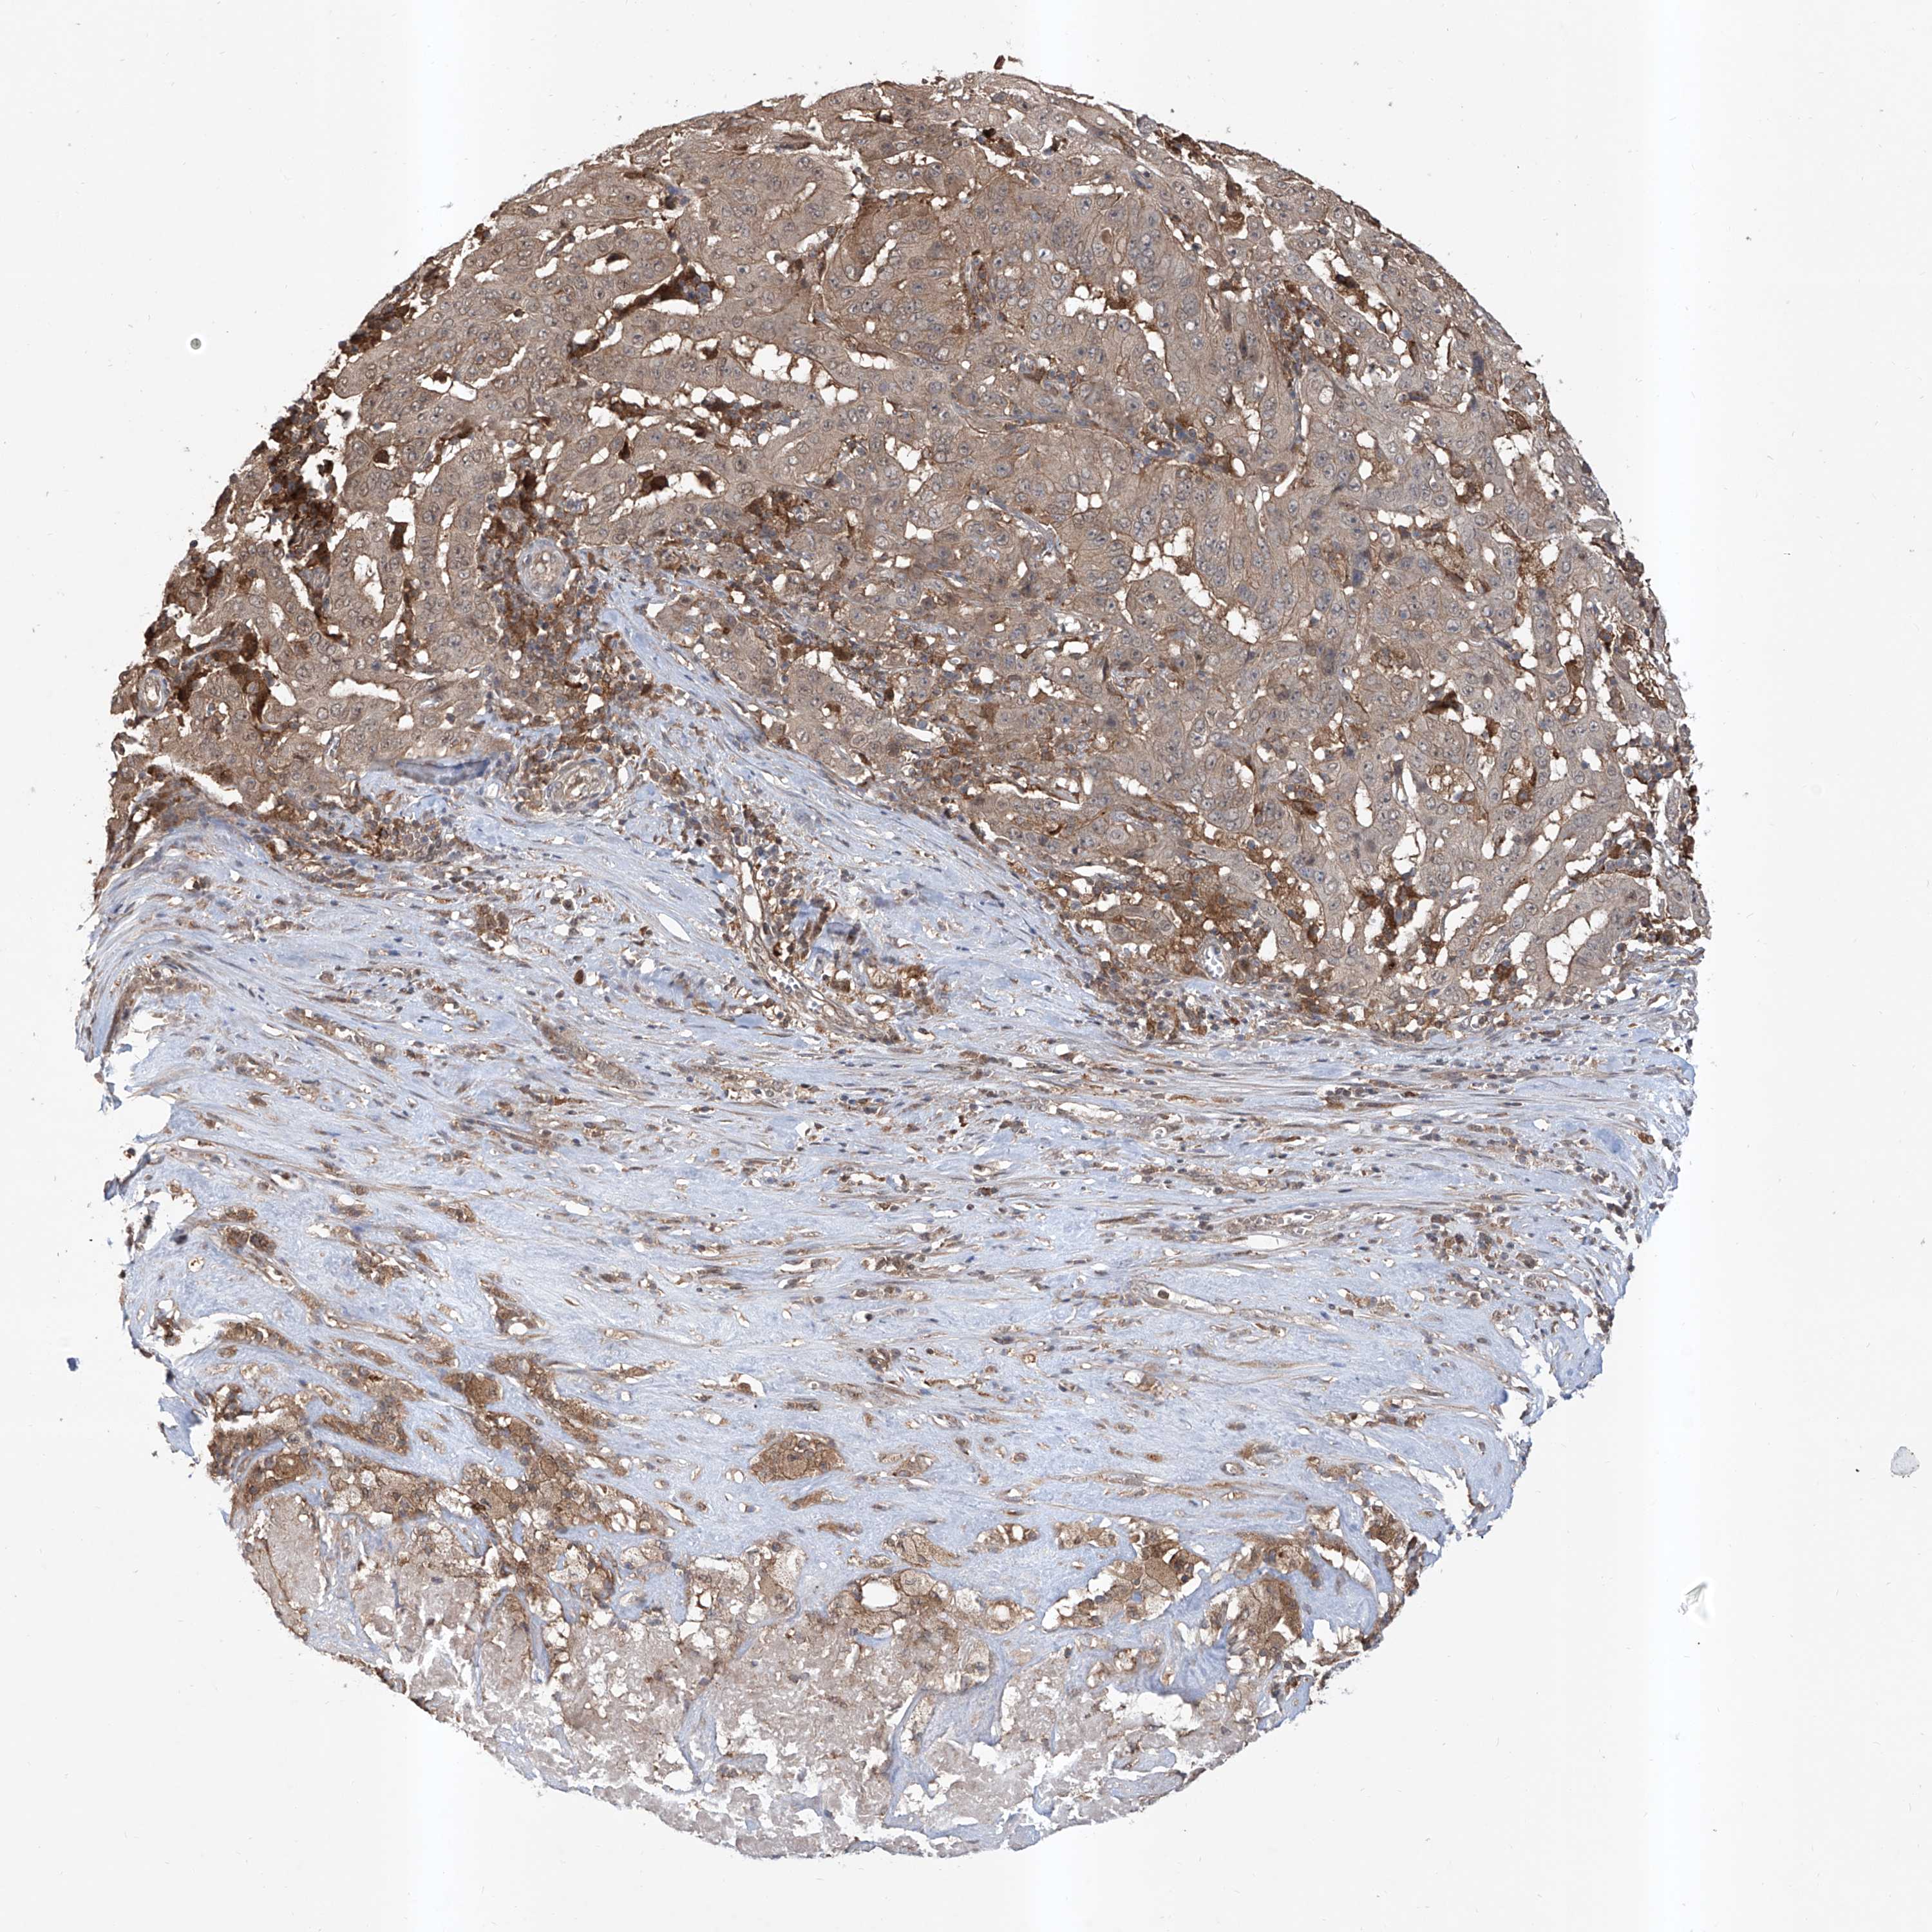

PANCREATIC CANCER - Protein expressioni

A mouse-over function shows sample information and annotation data. Click on an image to view it in a full screen mode. Samples can be filtered based on level of antibody staining by selecting one or several of the following categories: high, medium, low and not detected. The assay and annotation is described here.

Note that samples used for immunohistochemistry by the Human Protein Atlas do not correspond to samples in the TCGA dataset.

Antibody stainingi

Antibody staining in the annotated cell types in the current human tissue is reported as not detected, low, medium, or high, based on conventional immunohistochemistry profiling in selected tissues. This score is based on the combination of the staining intensity and fraction of stained cells.

Each image is clickable and will lead to virtual microscopy that enables deeper exploration of all samples and also displays staining intensity scores, fraction scores and subcellular localization as well as patient and tissue information for each sample.

Antibody HPA028911

Antibody CAB037020

Staining

High

Medium

Low

Not detected

Intensity

Strong

Moderate

Weak

Negative

Quantity

>75%

75%-25%

<25%

None

Location

Nuclear

Cytoplasmic/membranous

Cytoplasmic/membranous,nuclear

Adenocarcinoma, NOS